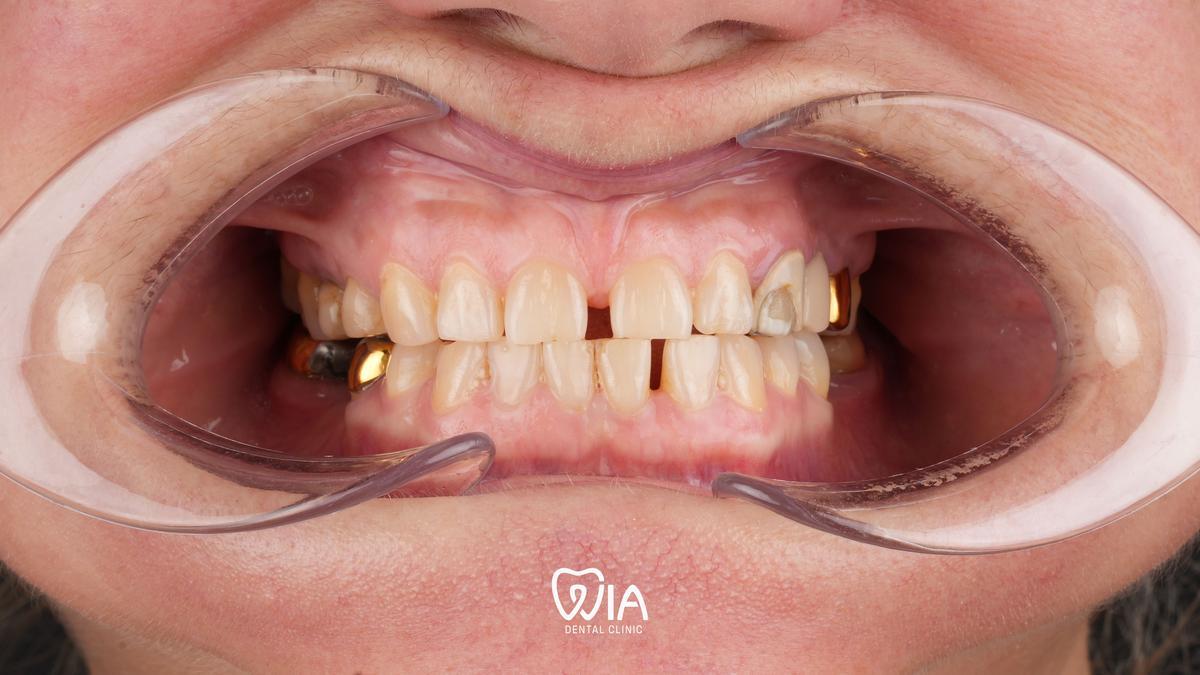

Dental Implants

Restore your smile with modern Swiss, German and American implants. Lifetime warranty included.

Dental Implants

Real results of our patients